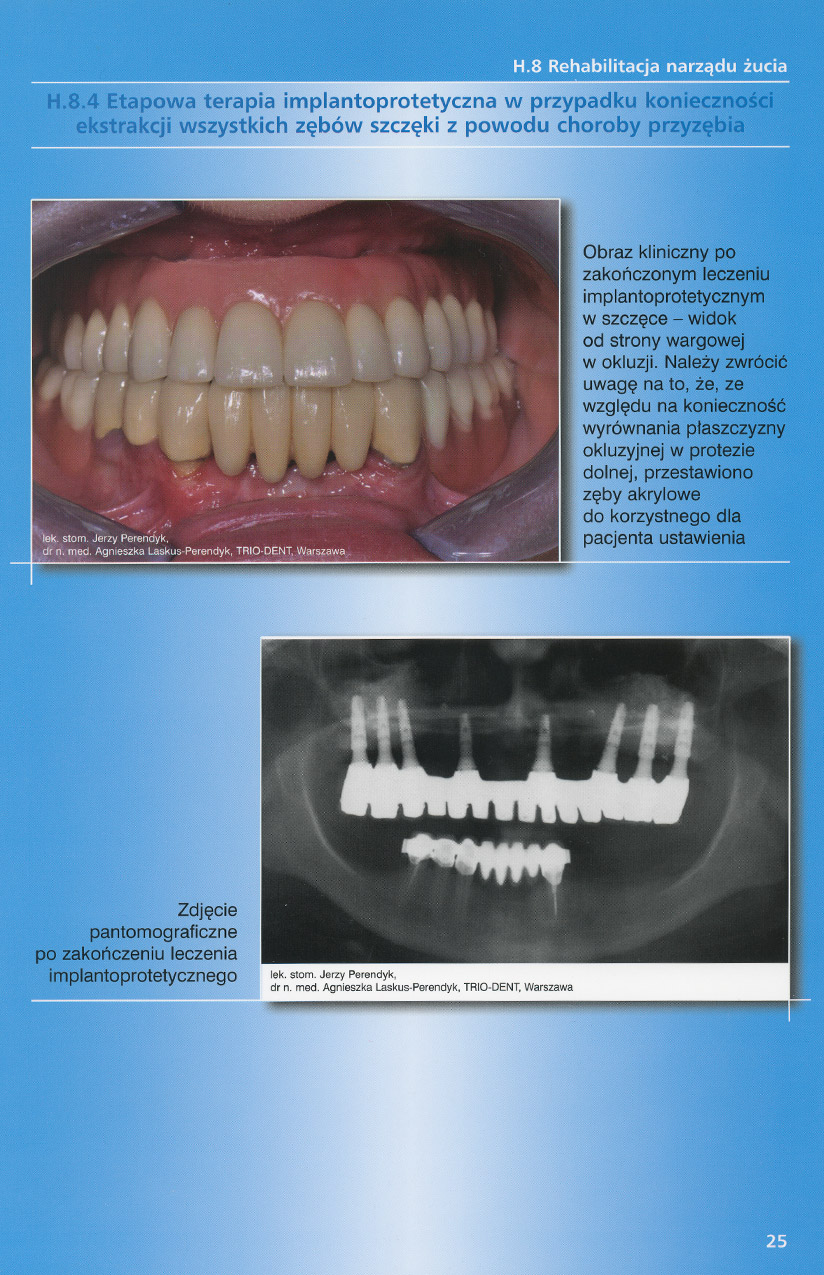

zobacz więcejGaleria przypadków klinicznych, obrazująca proces terapeutyczny od stanu wyjściowego aż do oddania ostatecznej pracy uzupełnienia brakującego uzębienia.